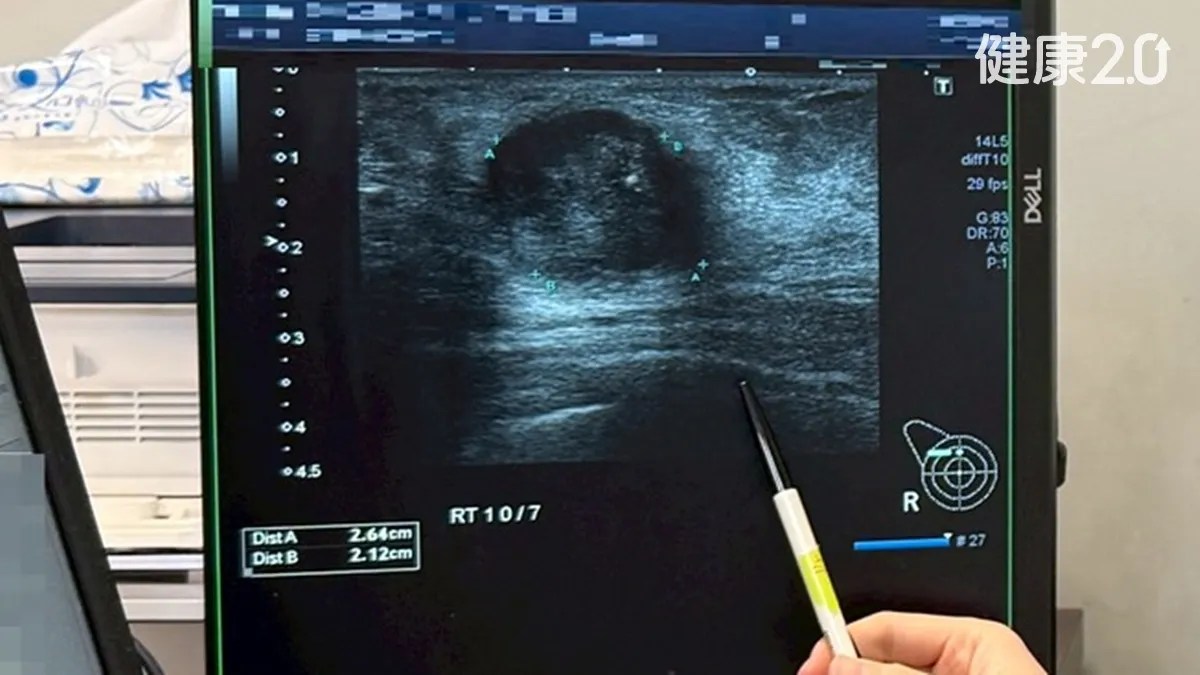

宋女士民國106年被診斷罹患肝癌合併雙側肺部轉移性病灶,曾經從宜蘭遠赴台北的醫學中心治療,不料效果不理想,肝臟腫瘤還暴增到18公分大,肺部的轉移病灶數量多到數不清,宋女士因此還有肝功能異常、黃疸、嚴重呼吸困難,整個人虛弱到無法行走,必須依賴氧氣瓶和輪椅,對任何醫療團隊來說,幾乎已經到了最糟的地步。

宋女士後來決定回到宜蘭治療,陽明交通大學附設醫院評估後,放棄使用標靶藥,改用傳統化療,令人意外的是2個月後就將肝臟大腫瘤和肺部數百顆轉移性腫瘤縮小到幾乎全消失,腫瘤指數從80.4降到正常值7.1以下,終於讓她恢復正常的生活能力,並持續定期追蹤。

不料111年8月,宋女士腫瘤指數再度升高到197,電腦斷層掃描發現肝臟有1.2公分大的新腫瘤,這次院方討論後,決定採用放射線治療搭配化療,這次新的腫瘤再度消失,腫瘤指數又恢復正常,今年11月的檢查顯示沒有復發。